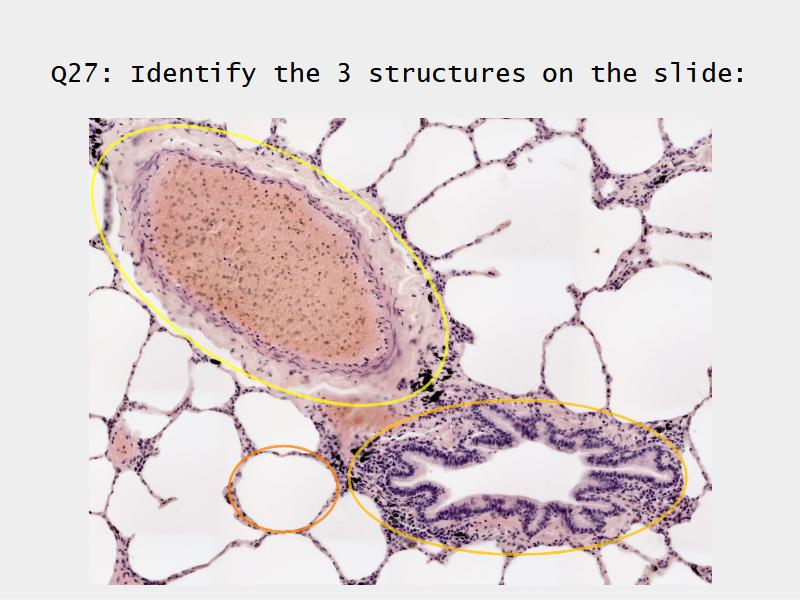

Slides: Respiratory System

- Slide 72 & 74: Lung

Bronchi - Transitions

- Intrapulmonary bronchi

- Irregular cartilage

- Respiratory epithelium

- Glands

- Bronchioles

- Smooth muscle REPLACE cartilage

- Ciliated columnar > Ciliated cuboidal

- NO glands - goblet cells -> secretory cells

- Terminal bronchioles

- Smooth muscle

- Ciliated cuboidal epithelium

- Secretory cells

- Respiratory bronchioles

- Conducting -> Respiratory

- Simple cuboidal epithelium

- Secretory cells

- Alveoli

Lungs